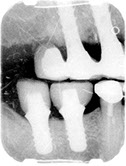

Before/After Photos